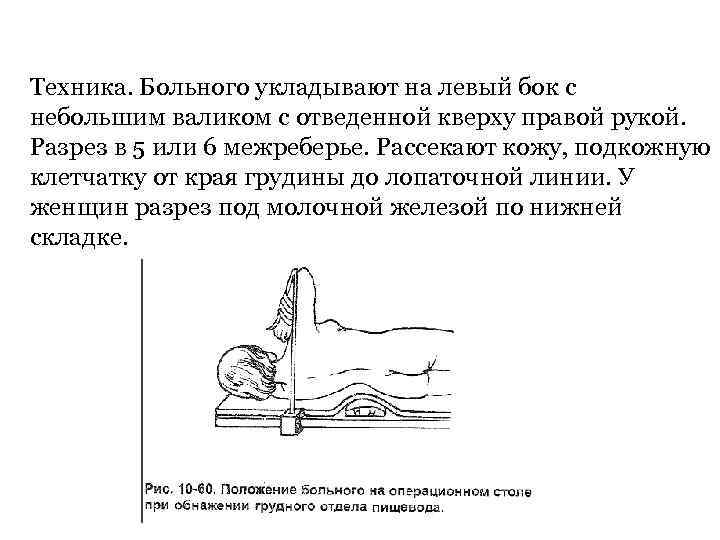

Техника. Больного укладывают на левый бок с небольшим валиком с отведенной кверху правой рукой. Разрез в 5 или 6 межреберье. Рассекают кожу, подкожную клетчатку от края грудины до лопаточной линии. У женщин разрез под молочной железой по нижней складке.

Техника. Больного укладывают на левый бок с небольшим валиком с отведенной кверху правой рукой. Разрез в 5 или 6 межреберье. Рассекают кожу, подкожную клетчатку от края грудины до лопаточной линии. У женщин разрез под молочной железой по нижней складке.